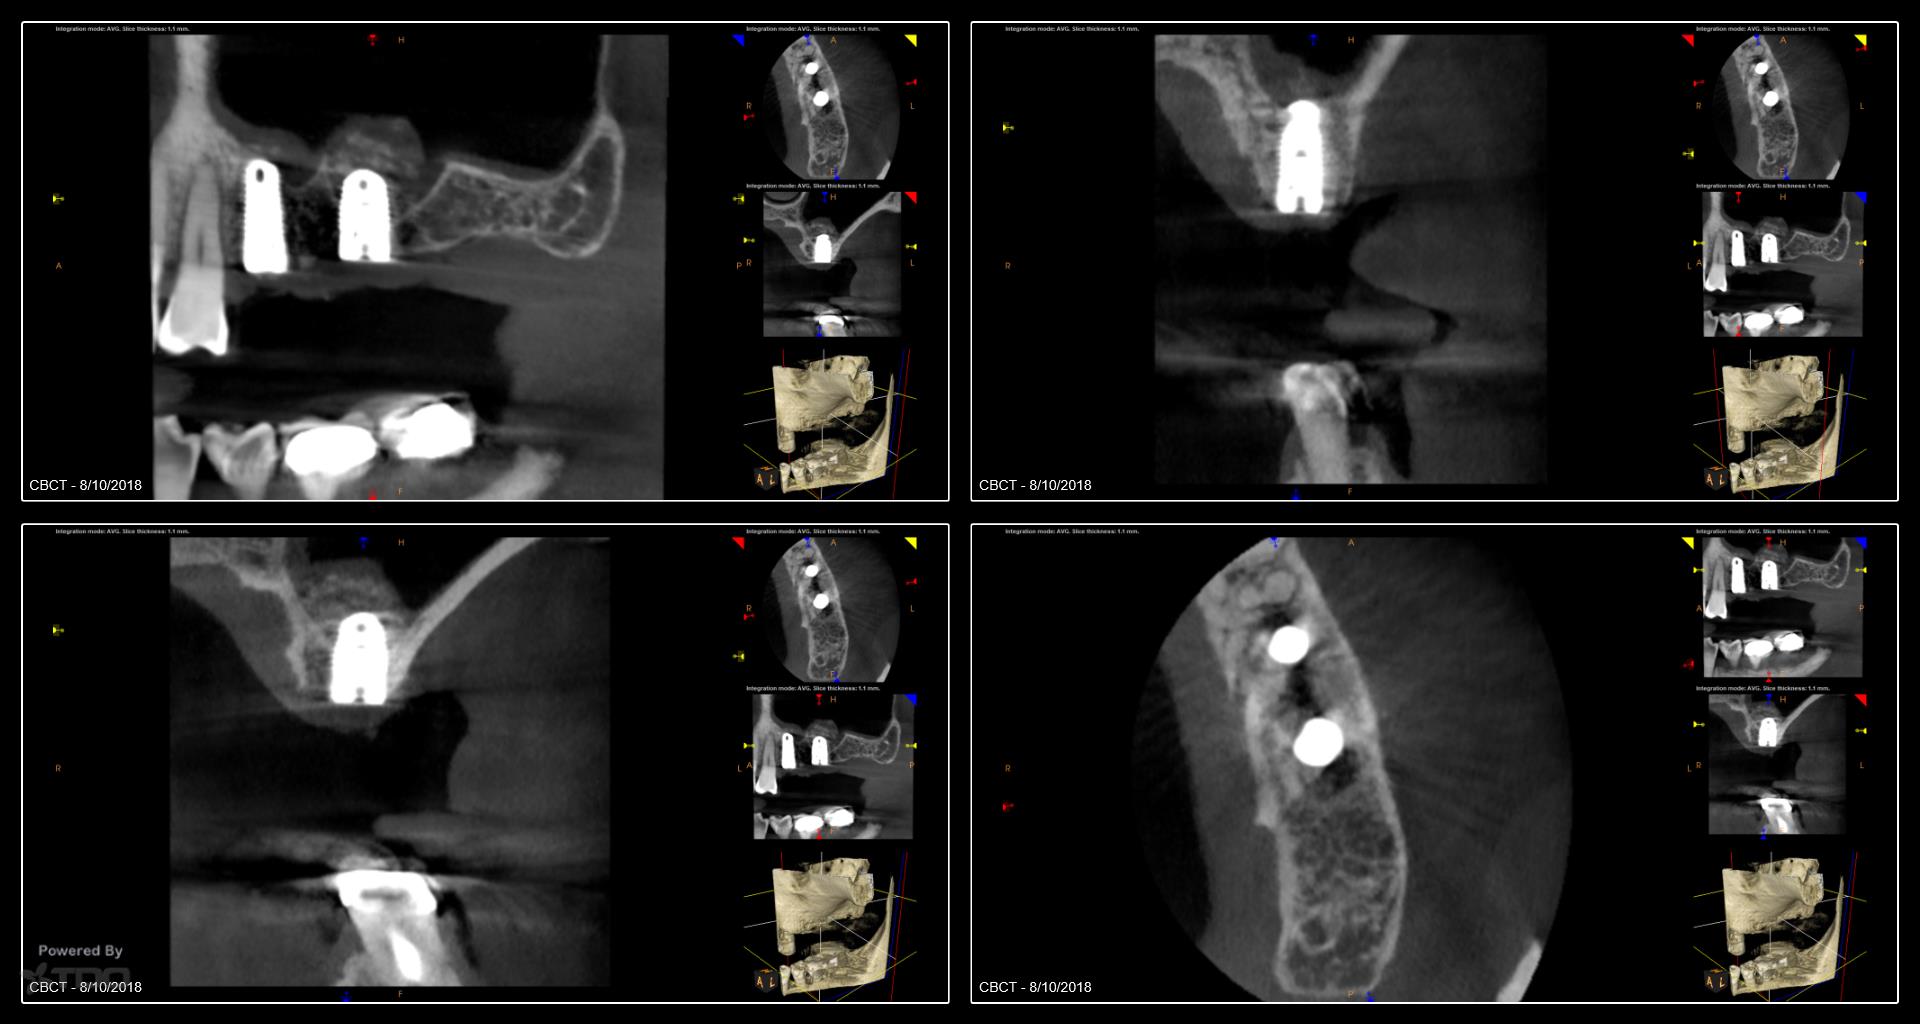

I began seeing this patient in 2014. Tooth #14 was diagnosed with a vertical root fracture at that time and the tooth was removed and the site grafted. He then presented in 2015 with a VRF of #15. It was removed and we discussed an implant in the #14 site. He did not follow up with the implant. He presented earlier this year with a vertical root fracture of #13. The tooth was removed in April and implants were placed today. Internal sinus lifts were performed for both #’s 13 and 14. I will uncover in 4 months. We have also discussed the importance of a night guard. Hopefully he will follow through with the guard. -Charles